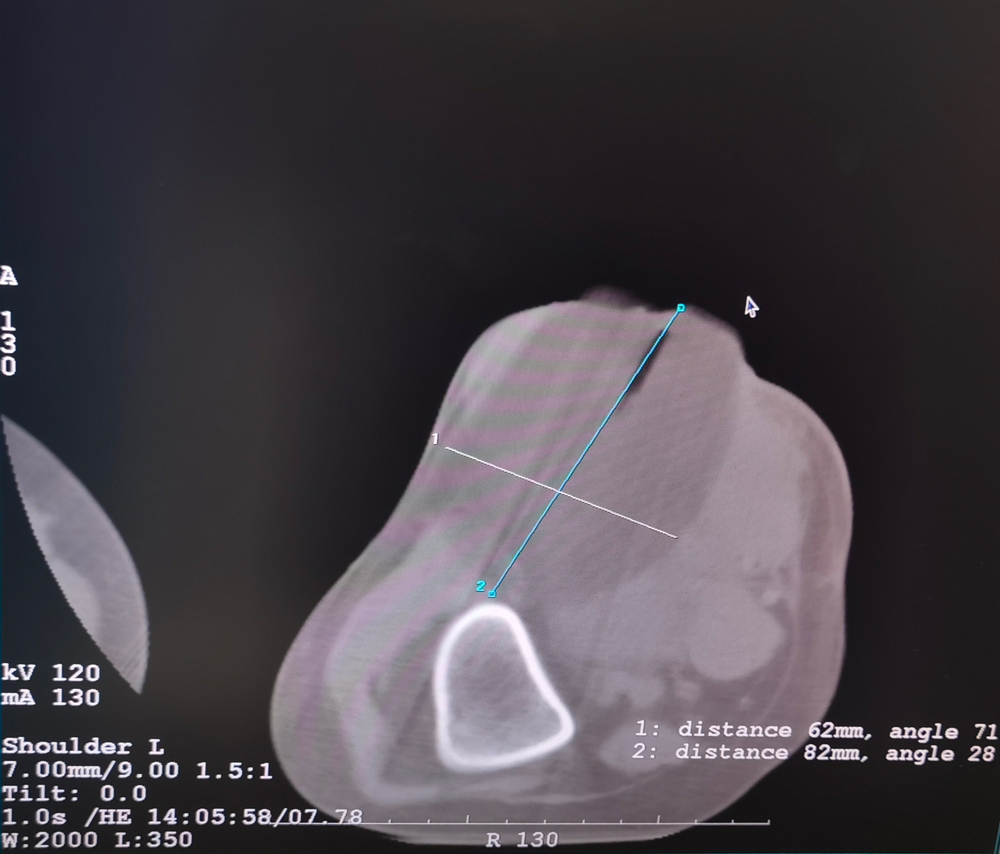

女,56歲,肺轉移瘤,骶骨、左側肋骨各一轉移灶,病灶大小均為5cm。骶骨轉移灶、肋骨轉移灶各進行2個凍融循環。患者術后狀況良好。

女,42歲,復發性脂肪瘤,病灶位于右側膝關節,直徑大小13cm。采用雙針方案,共進行6個凍融循環,最大冰球直徑達8.2cm,術中多方位治療全面覆蓋病灶范圍。患者術后狀況良好。